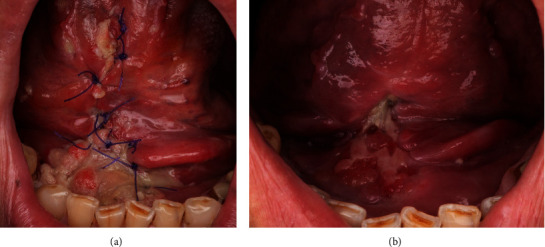

背景:消融手术后,口腔缺损的重建对于确保最佳功能和美观效果至关重要。本研究旨在回顾性分析舌下腺皮瓣(SGF)在口腔软组织重建中的有效性和并发症发生率。本研究讨论了舌下腺皮瓣的采集过程以及该皮瓣的优势和局限性。材料和方法:研究组包括 13 名接受 SGF 软组织重建术的肿瘤患者。根据组织病理学方面、术后并发症和疗效对患者的病历进行了评估。8名患者(61.5%)进行了口底重建,5名患者(38.5%)进行了下牙龈重建。手术结果平均 2 周内缺损上皮完全闭合。观察期从 1 个月到 33 个月不等,平均为 11.5 个月。一名患者(7.7%)出现皮瓣部分坏死和溃疡。此外,一名患者(7.7%)出现术后出血,另一名患者(7.7%)出现伤口开裂和脓肿形成。有一名患者(7.7%)观察到癌症局部复发。结论SGF可成功重建下牙龈和口底的中小型缺损。并发症发生率相对较低。

Background: Following ablative surgery, the reconstruction of oral cavity defects is essential to ensure optimal function and aesthetically acceptable outcomes. The purpose of this study was to retrospectively analyze the effectiveness and complication rates of the sublingual gland flap (SGF) in oral soft tissue reconstruction. The procedure for harvesting SGF and the strengths and limitations of the flap are discussed. Materials and Methods: The study group consisted of 13 patients suffering from oncological diseases who underwent soft tissue reconstruction with SGF. The patient's medical charts were evaluated based on histopathological aspects, postoperative complications, and outcomes. Reconstruction of the floor of the mouth was performed in 8 patients (61.5%) and lower gingiva in 5 patients (38.5%), respectively. Results: Complete epithelialization with closure of the defect was achieved within an average of 2 weeks. The observation period ranged from 1 to 33 months, with an average duration of 11.5 months. Partial flap necrosis and ranula occurred in one patient (7.7%). Furthermore, postoperative bleeding was observed in one patient (7.7%), and wound dehiscence and abscess formation were noted in another (7.7%). Locoregional recurrence of the cancer was observed in one case (7.7%). Conclusions: The SGF is effective for achieving successful reconstruction of small- and medium-sized defects in the lower gingiva and floor of the mouth. The complication rate is relatively low.